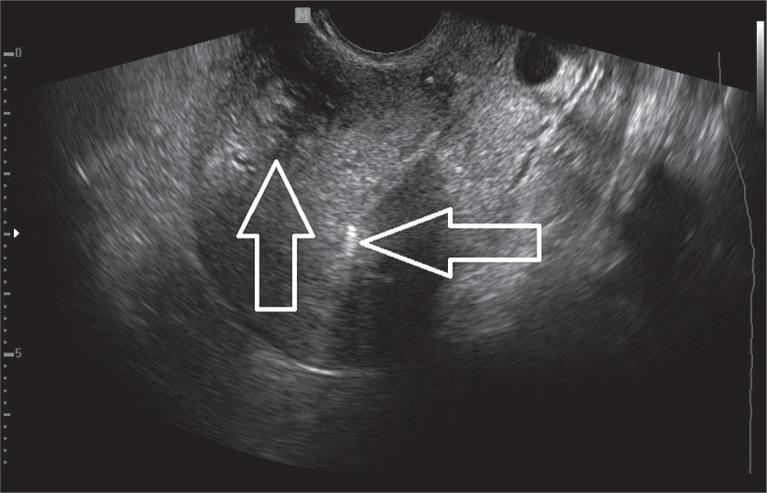

Uterine fibroids are considered to be the most frequently occurring tumours in females. The majority of fibroids do not require any treatment. When symptomatic, the major ailments include abnormal uterine bleeding, painful menstruation, pelvic pressure or pain, urinary problems, constipation, infertility, and recurrent pregnancy loss. Surgery remains a mainstay of symptomatic uterine fibroids therapy; however, minimally-invasive techniques and pharmacological management have become more available. The levonorgestrel intrauterine system (LNG-IUS) is a T-shaped device with a vertical stem containing a reservoir of levonorgestrel and is widely known for its contraception effect. Moreover, the non-contraceptive benefits of the LNG-IUS have been previously confirmed by numerous studies. LNG-IUS causes reduction of the duration and the amount of menstrual bleeding, with minimal side effects due to release of hormones at the targeted organ. Currently, results from systematic reviews show that LNG-IUS may be an effective and safe treatment for symptomatic uterine fibroids in premenopausal women. However, further studies are required to consolidate the usage of LNG-IUS in the treatment of symptomatic uterine fibroids.

子宫肌瘤被认为是女性中最常见的肿瘤。大多数肌瘤不需要任何治疗。出现症状时,主要病症包括子宫异常出血、痛经、盆腔压迫感或疼痛、泌尿系统问题、便秘、不孕以及反复流产。手术仍然是有症状子宫肌瘤治疗的主要手段;然而,微创技术和药物治疗变得更加可行。左炔诺孕酮宫内节育系统(LNG-IUS)是一种T形装置,其垂直杆部含有左炔诺孕酮储存器,因其避孕效果而广为人知。此外,LNG-IUS的非避孕益处此前已得到众多研究的证实。LNG-IUS可减少月经出血的持续时间和出血量,由于激素在靶器官释放,副作用极小。目前,系统评价的结果表明,LNG-IUS可能是治疗绝经前有症状子宫肌瘤的一种有效且安全的方法。然而,需要进一步研究以巩固LNG-IUS在有症状子宫肌瘤治疗中的应用。